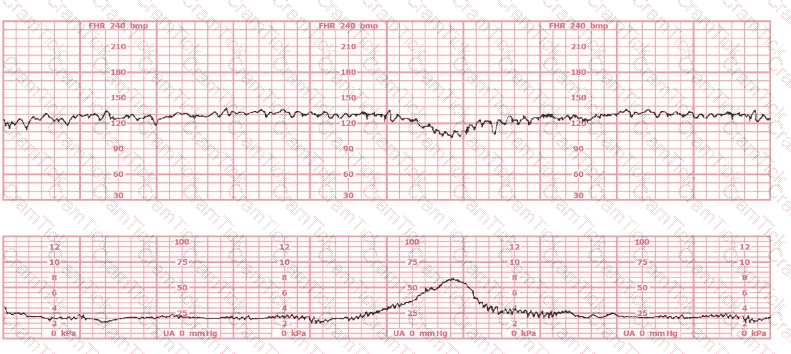

A 30-year-old woman (G2P0) is experiencing preterm labor at 26-weeks gestation. She is receiving magnesium sulfate for neuroprotection. Her external fetal monitoring tracing over the past 30 minutes is shown. The next step would be to: